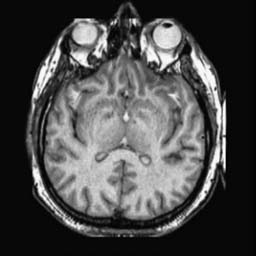

To demonstrate the effectiveness and efficiency of the proposed image fusion method , we conduct a set of comparative experiments on three image datasets. The first is composed by 8 pairs of multi-modal medical images and the second one contains 15 pairs of multi-focus gray or color natural images. These two datasets are often used in many related papers and some examples are shown in Figure 3(a) and Figure 3(b). The third one is a new multi-focus cervical cell image dataset collected by ourselves, which consists of 15 groups of color images and each group contains a series of multi-focus cervix cell images with size of or , etc. Some source examples are shown in Figure 3(c). Our source code implemented in C++ along with the new multi-focus cervical cell image dataset is available online.

We first evaluate the performance of the proposed method under varying total number of octaves and number of layers sampled per octave. The fused images of a pair of multi-modal medical images with different and are shown in Figure 4. In this example, on the one hand, when only 1 or 2 octaves are involved in constructing the DoG pyramid, the fused images fail to keep the integrity information of large size objects (e.g. eyeballs), while by increasing the value of , the integrity information of eyeballs is preserved. On the other hand, although not as significant as the increase of octave numbers , the fused image can contain more details by the increase of layer numbers . The corresponding objective quality metrics are shown in Figure 5. As shown in Figure 5(a), most of the metric values are improved as the number of octaves increases with the fixed layer numbers 3 in the global tendency and each of them tends to be stable when the number of octaves is 5. To get a relatively good quality from Figure 5(b), we can notice that some of the metric values can get a good performance when the number of layers is 3, such as the MI, SSIM, QI and VIF, though there are only a little change of all the metric values by increasing the number of layers with the fixed octave numbers 5. Because it will result in more computation burden with the increase of the value and , and for different kinds of source images, there are different performance with the diverse parameter settings. To get a trade-off between them in our experiments, we set for the multi-modal dataset, for the natural datasets and for the multi-focus cell dataset, respectively.

Figure 6 shows the fused images obtained by different methods with the multi-modal source images shown in Figure 3(a). As shown in these figures, the proposed method can produce images which preserve the complementary information of different source images well. Moreover, due to the scale-invariant structure saliency selection, our method can keep the integrity information of large size objects and the visual details simultaneously. Although the fused image generated by other methods can also capture the details to some extent, all of them fail to keep the integrity information of large size objects such as the eyeballs. Furthermore, from Figure 6(k)-6(t), the DTCWT, GFF, IM and NSCT methods may decrease the brightness and contrast while the proposed method can preserve these features and details without producing visible artifacts and brightness distortions.